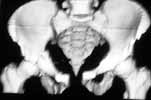

Middle aged male who was injured when a log of wood fell on him ina saw mill. Haemodynamically patient stable. No visceral injuries detected. The following musculoskeletal injuries detected: 1) Closed fracture femur. 2) Pubic symphysis disruption. 3) Right inf pubic rami fracture. 4) Right acetabular fracture. Head of femur located. 5) Right Sacroiliac joint anterior opening.

The pelvic injury appears to be an APC1 (AP Compression) by the Young-Burgess classification.

Dalal, Young, Burgess and Siegal report a 9% incidence of GU injury with APC1.

Further pelvic AP compression by driving a fracture table perineal post against an injured perineum with possible urethral, bladder, rectal and/or pudendal nerve attenuation sounds risky.